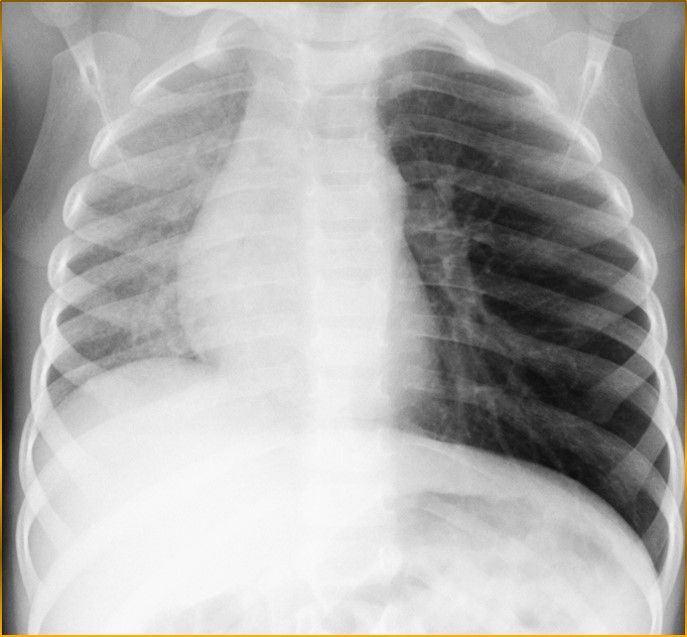

Radiografia del Torace in inspirio

Si intravede alterazione della diafania del campo polmonare sinistro

Radiografia del Torace in Espirio

Si vede chiaramente la mancata espulsione dell'aria dal campo polmonare a sinistra per occlusione bronchiale